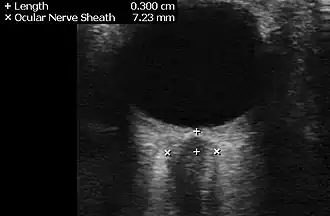

Ultrasound of the optic nerve showing IIH[17]

The diagnosis may be suspected on the basis of the history and examination. To confirm the diagnosis, as well as excluding alternative causes, several investigations are required; more investigations may be performed if the history is not typical or the person is more likely to have an alternative problem: children, men, the elderly, or women who are not overweight.[8]